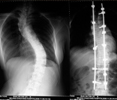

椎管狹窄症正位X線片常顯示腰椎輕度側彎,關節突間關節間距離變小,有退行性改變。側位X線片顯示椎管中央矢狀徑常小,小於15mm就說明有狹窄的可能。必要時可進行腰椎穿刺,奎肯試驗,腦脊液化驗,及脊髓造影。脊髓造影是診斷本症的可靠方法。正位片可清楚顯示硬脊膜腔的大小,如出現有條紋狀或鬚根狀陰影,表示馬尾神經根有受壓現象,或全梗阻,如影柱呈節段性狹窄或中斷,表示為多發性或全梗阻。